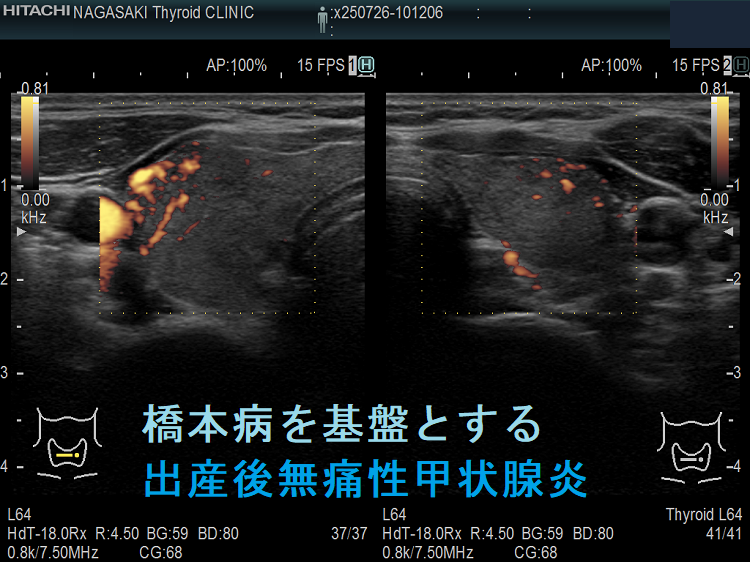

橋本病を基盤とする出産後無痛性甲状腺炎(水平断) ドプラーモード;無痛性甲状腺炎であるため、内部血流は少ない。

橋本病を基盤とする出産後無痛性甲状腺炎下甲状腺動脈の収縮期最大血流速度(ITA-PSV);無痛性甲状腺炎であるため、下甲状腺動脈の収縮期最大血流速度(ITA-PSV)は低値